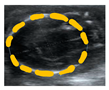

| Cranial circumference (CC) | Elipse around DBP as transversal diameter and a longitudinal diameter touching the occipital bone | mm (perimeter), mm2 (area) | ![]() |